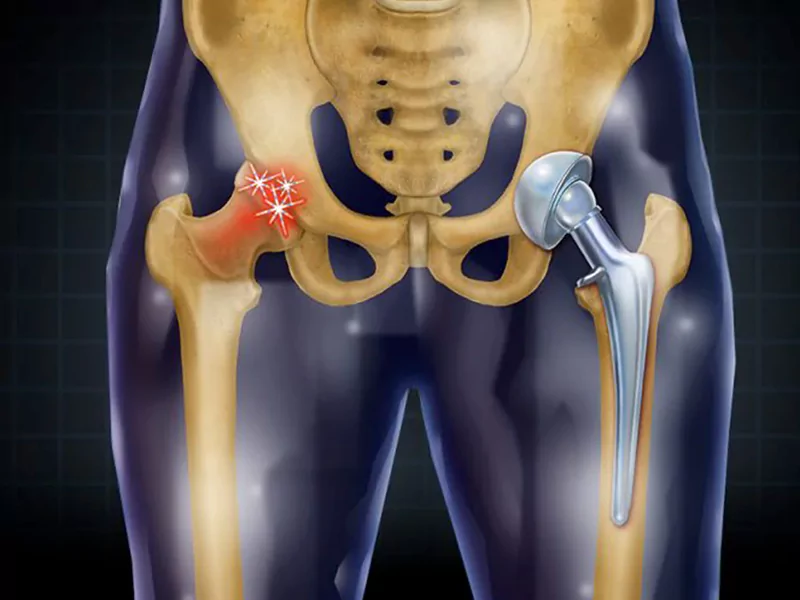

دکتر افشاریان دارای برد تخصصی ارتوپدی و فلوشیپ جراحی لگن و مفصل ران از دانشگاه‌ های معتبر ایران هستند. ایشان با بهره‌ گیری از جدیدترین تکنیک ‌های جراحی، موفقیت ‌های چشمگیری در زمینه ‌های مختلف جراحی لگن داشته‌ اند. از جمله این روش ‌ها می‌توان به جراحی تعویض کامل مفصل لگن، جراحی ‌های بازسازی لگن، درمان شکستگی ‌های پیچیده ناحیه لگن و تصحیح دفورمیتی‌ های این ناحیه اشاره کرد.

مطب دکتر افشاریان مجهز به پیشرفته ‌ترین تجهیزات تشخیصی و درمانی است. ایشان از تکنیک ‌های کم‌ تهاجمی در جراحی ‌ها استفاده می‌ کنند که منجر به کاهش درد پس از عمل، دوره نقاهت کوتاه ‌تر و بازگشت سریع ‌تر بیمار به زندگی عادی می ‌شود. استفاده از ناوبری کامپیوتری در حین جراحی ‌های تعویض مفصل، دقت عمل را به میزان قابل توجهی افزایش داده است.